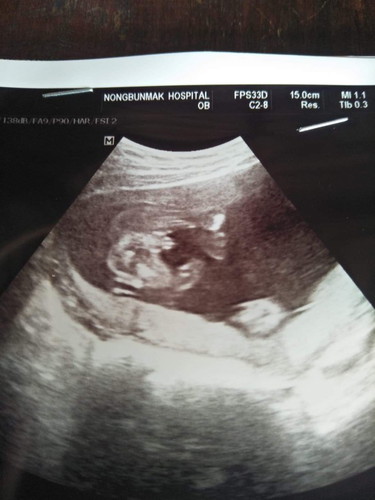

ชายหรือหญิงคะ

แม่ๆว่าเพศชายหรือหญิงคะถ้าซาวออกมาแบบนี้ ถามเพื่อความมั่นใจคะ

หมอบอกว่าเห็นจู๋มาแต่ไกลเลย ผู้ชายเหมือนกันเลยค่ะ

เพศชายค่ะคุณแม่ หน่อไม้แหลมเฟี้ยวเลย

น่าจะชายนะค่ะเห็นอะไรไม่รุ้โผล่ด้วย

ชายน่ะค่ะเห็นจุ๊ดจู๋เลย

เด่นชัดมากเรยค่ะแม่ชายจ้า

ชายจร้า7เดือนแล้วชัดมาก